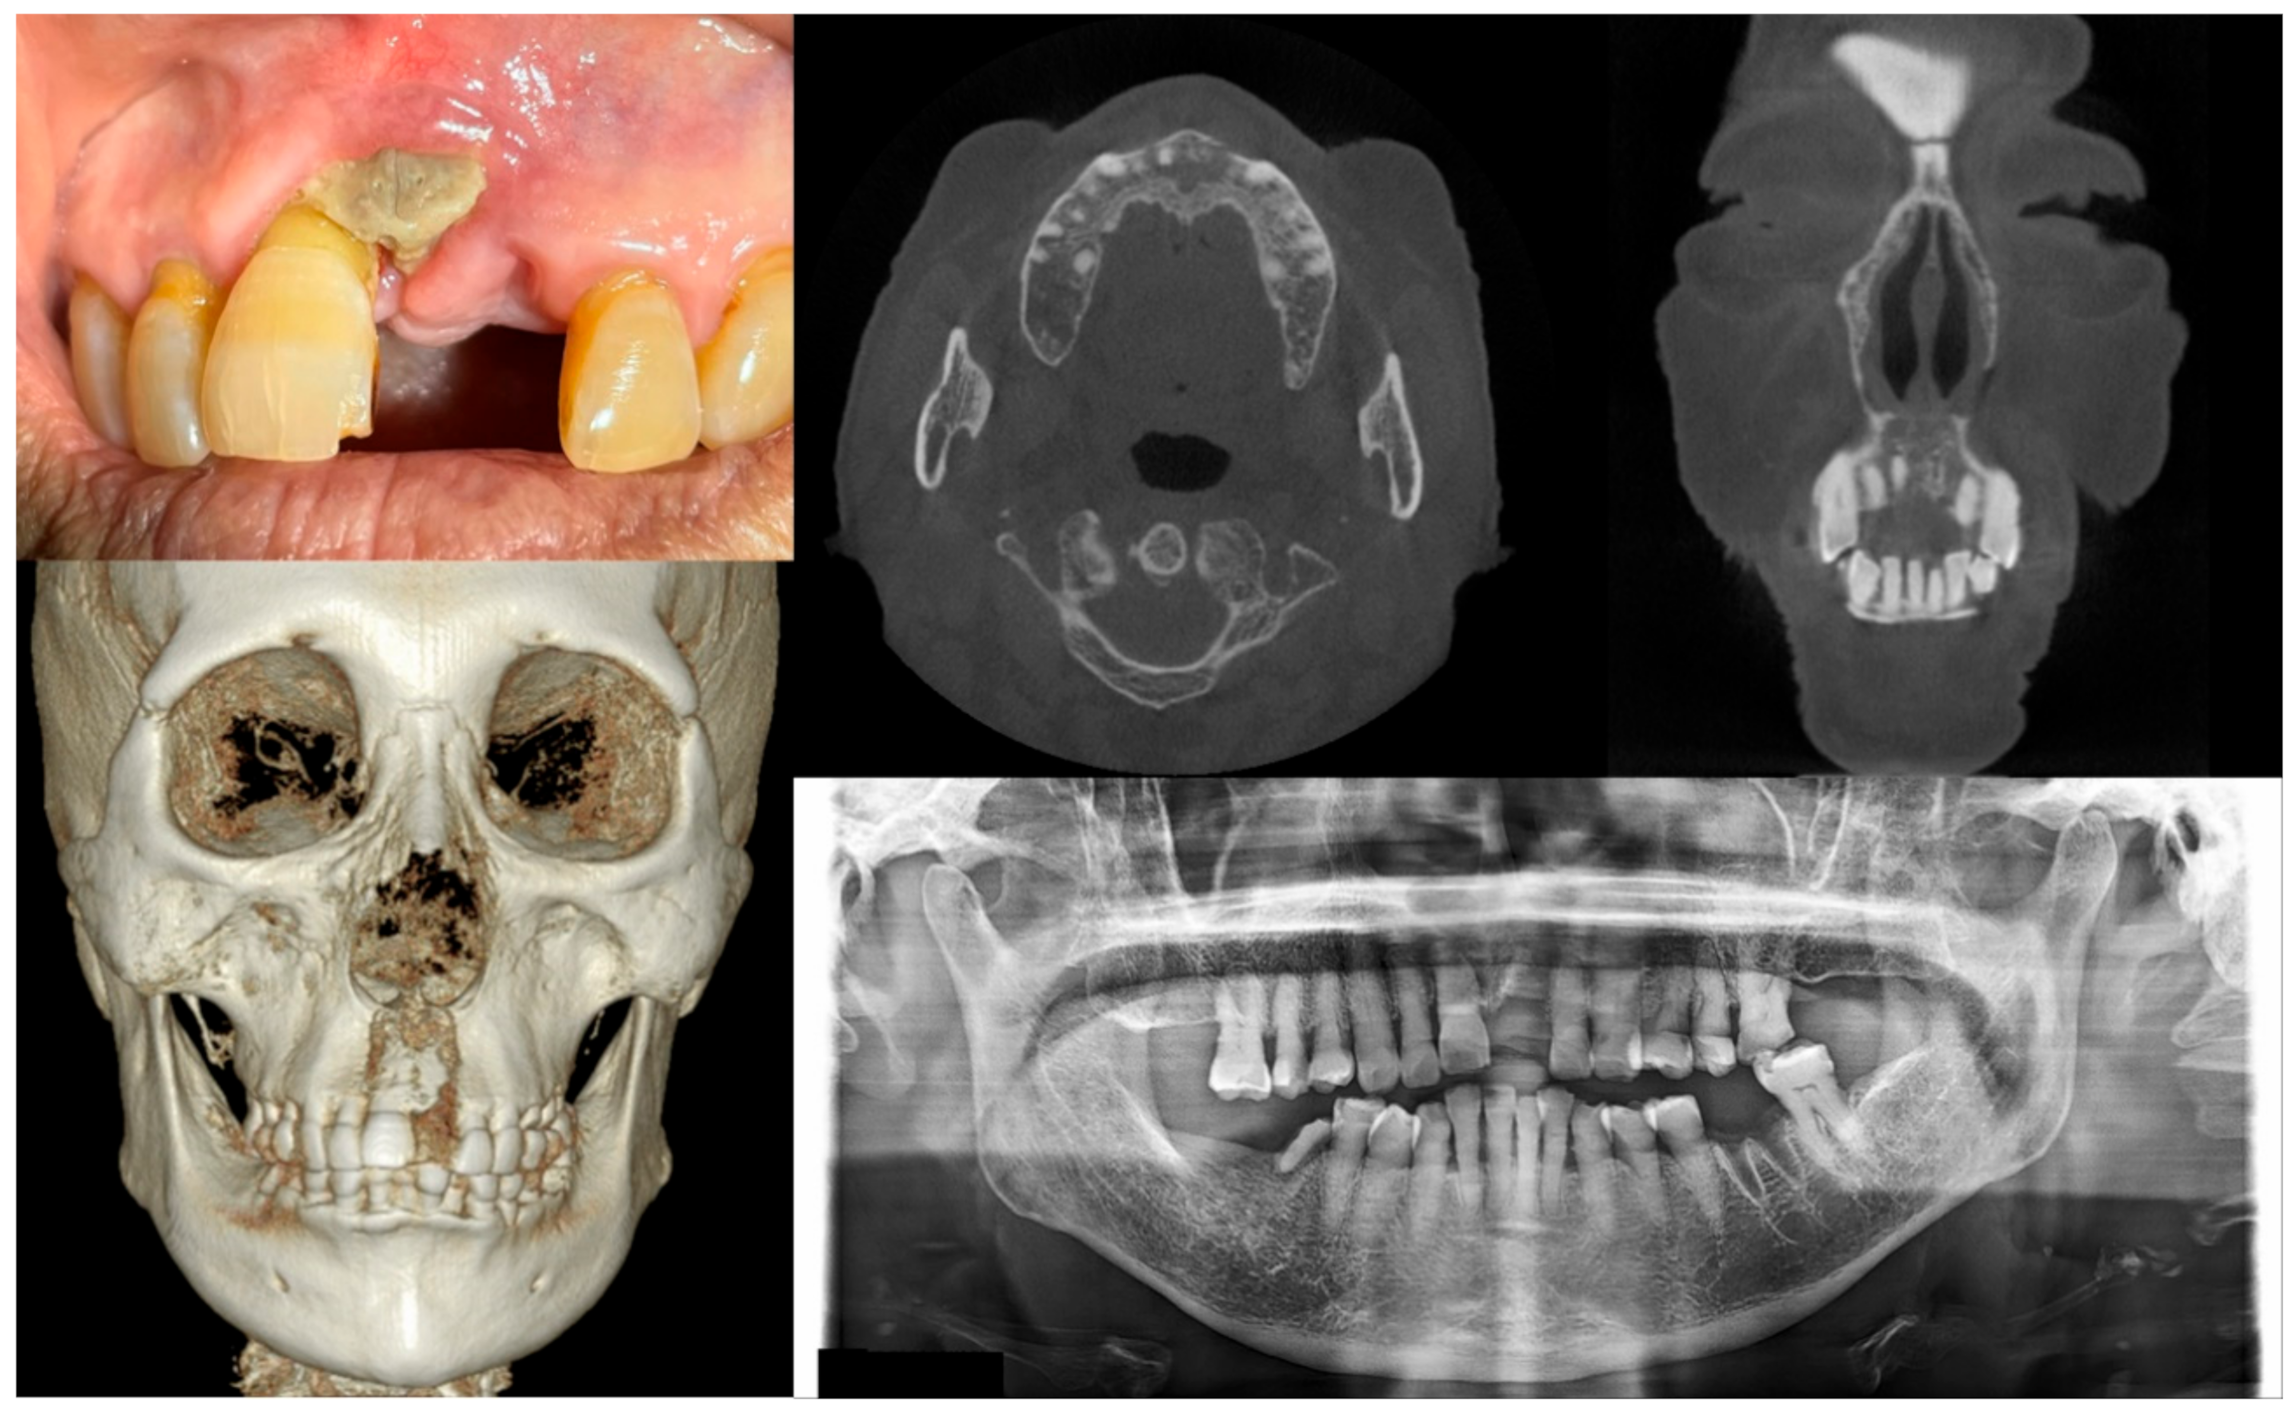

Figure 2.

Case 2 with MRONJ Stage 1: Clinical photo, panoramic view, and computed tomography imaging including three-dimensional reconstruction showing exposed alveolar bone on the anterior maxillary area. An 89-year-old female patient with a history of oral alendronate for more than four years and intravenous administration of denosumab for one year showed the exposed bone after extracting the left upper central incisor three months ago. She reported no symptoms such as pain other than exposed bones. There was no sign of infection, including pus discharge on the exposed bone.